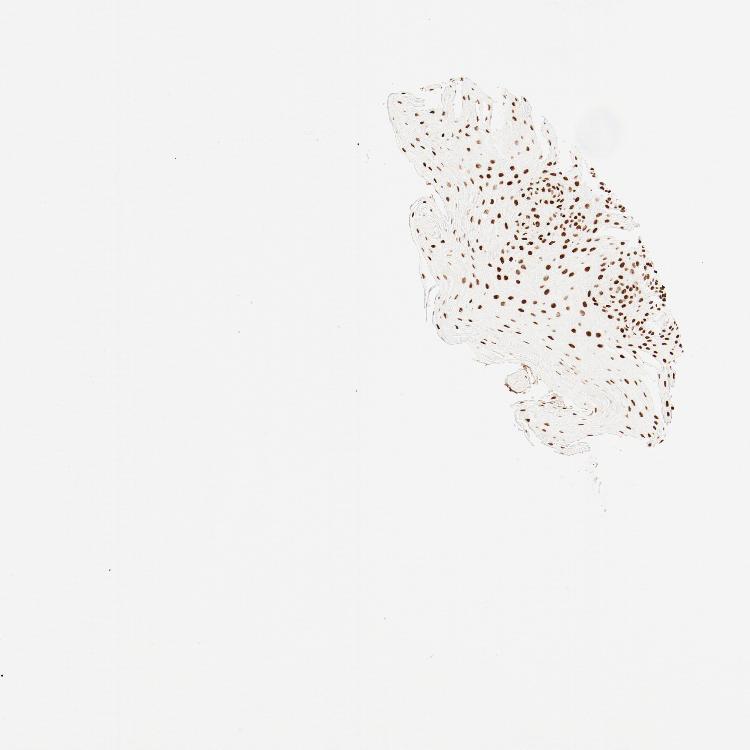

TISSUE PRIMARY DATA ORAL MUCOSA Show tissue menu

ORAL MUCOSA - Antibody stainingi

Antibody staining in the annotated cell types in the current human tissue is reported as not detected, low, medium, or high, based on conventional immunohistochemistry profiling in selected tissues. This score is based on the combination of the staining intensity and fraction of stained cells.

Each image is clickable and will lead to virtual microscopy that enables deeper exploration of all samples and also displays staining intensity scores, fraction scores and subcellular localization as well as patient and tissue information for each sample.

Antibody HPA021213Antibody CAB004321

Squamous epithelial cells HighHigh